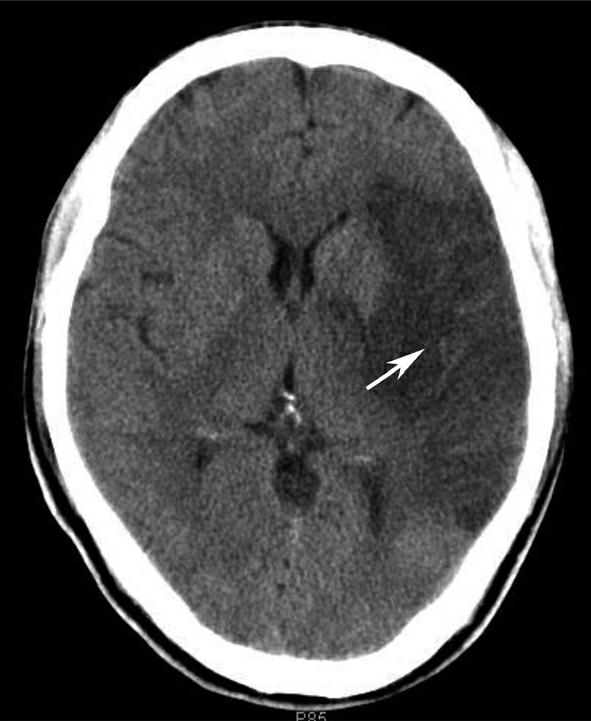

图1-2-28 苍白球生理性钙化

A.双侧苍白球对称性钙化,呈高密度影(箭);B.左侧苍白球钙化(箭),右侧苍白球钙化不明显